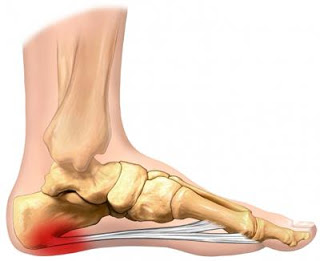

Are you experiencing pain with walking? Do you get burning in the arch of your foot? Do you have sharp heel pain? This will go over the major injuries and causes of pain that you need to be aware of to help you be aware of conditions, solving your pain, and to help...

What type of shoe is best for my Plantar Fasciitis? Plantar Fasciitis can be very painful condition and getting in the proper shoe is essential to your recovery process. Whether you are a runner or working 8 hours a day in the office, proper arch support for plantar...

What are some of the risk factors or causes that can lead to Plantar Fasciitis? The cause of heel pain, or plantar fasciitis, is multi-factoral and actually poorly understood, but here are some risk factors that have been proven to contribute to the cause heel pain...